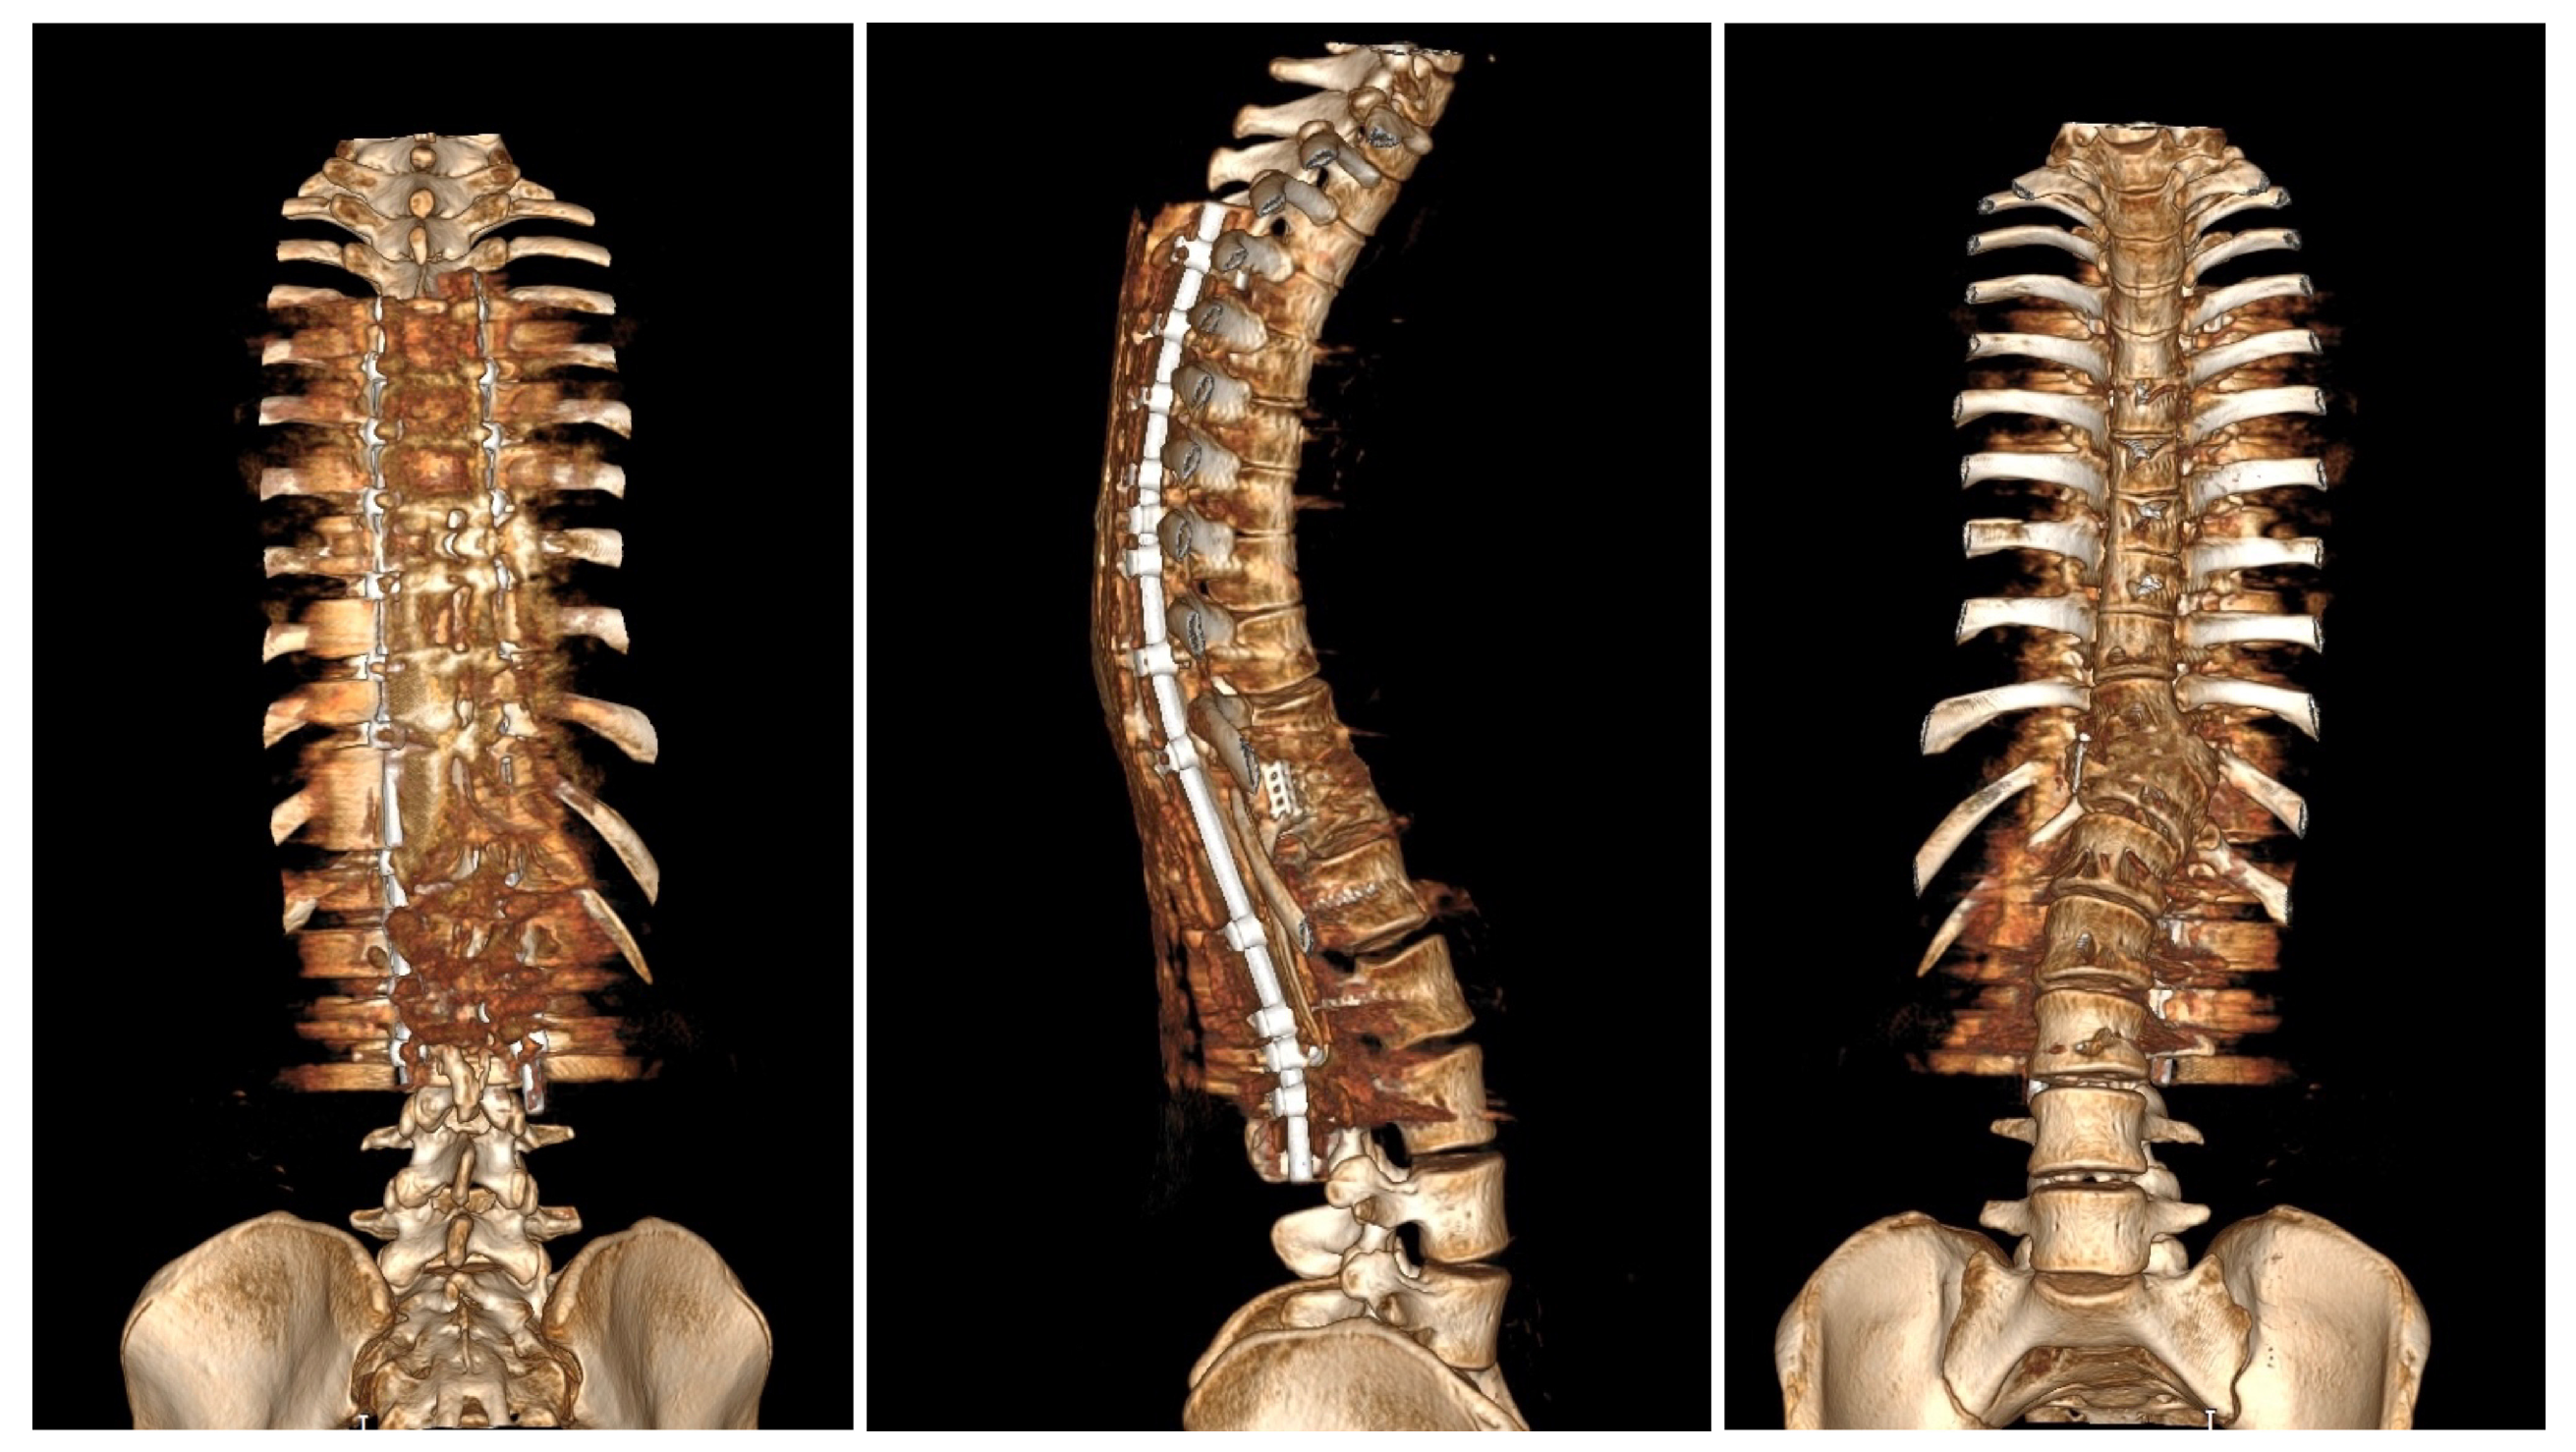

Postoperative imaging showed significant improvement in both three-dimensional planes (Figure 8).

Upon conducting a postoperative physical examination, it was observed that the patient’s shoulder symmetry and rib hump had improved significantly without any neurological or other complications. Figure 9 shows a significant improvement in the patient’s posture, sagittal balance (focal thoracic kyphosis from 108° to 43°), and coronal balance (from 63° to 25°). The patient was discharged 5 days after surgery; no brace was ordered. Figure 10 and Figure 11 show the X-rays and 3D-CT of the patient at the final follow-up.

Figure 11. 3D-computer tomography reconstruction of the whole spine of the 16-year-old female after undergoing surgical treatment at 2 years of follow-up. The pictures show spondylodesis of the posterior and anterior columns.